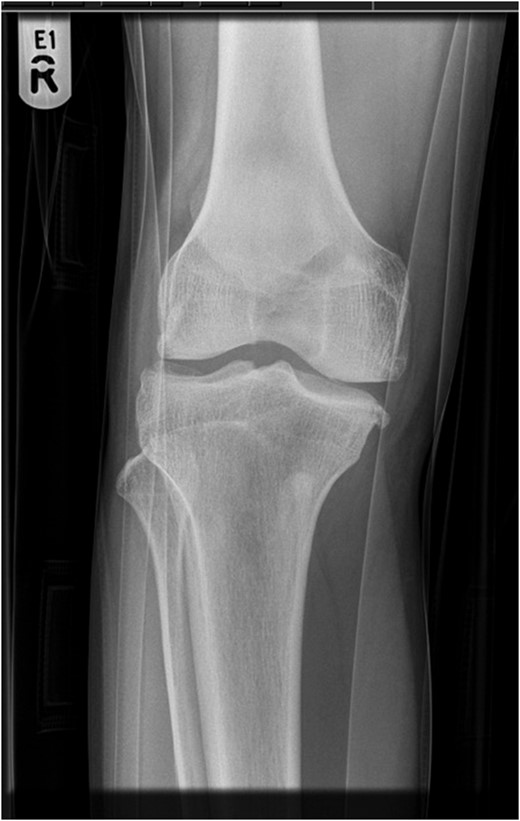

Superior patellar dislocation is a very rare pathology, which happens in middle age. We report a case of spontaneous superior patellar dislocation, which occurred at 30 years of age. Differential diagnosis is patellar tendon rupture, which could be reliably excluded by clinical examination and radiographs. Reduction manoeuvres should be tried with diluted intra-articular local anaesthetic for hydrodilatation to gain mechanical advantage. Splinting the knee in gentle flexion is recommended if general anaesthetic is employed. Recurrent dislocation or osteochondral fractures warrants surgical treatment.

A 30-year-old gentleman woke up with a sudden onset of knee pain. He had never experienced any knee problems in past. The emergency department referred him as a suspected patellar tendon rupture. History, examination and radiographs revealed a characteristic superior patellar dislocation. No obvious generalized ligament laxity, genu recurvatum or patella alta was found. Hydrodilatation of his knee was performed using 10 ml of 0.5% Chirocaine diluted in 20 ml of 0.9% normal saline. Dislocation was reduced successfully with gentle digital manipulation. Full pain free range of motion was demonstrated after reduction. He was discharged home the same day with no recurrence at 6 months.

Reduction can be attempted with intra-articular local anaesthetic, sedation, femoral nerve block and rarely general anaesthetic [7]. It is advised to immobilize knee in gentle flexion during recovery from general anaesthesia to avoid recurrence in perioperative period [4]. When awake, knee can be left free. Intra-articular local anaesthetic diluted in normal saline is recommended, giving analgesic as well as mechanical advantage, by pushing patella away from femur. This technique of getting a mechanical advantage has not been previously described in literature. If other analgesics fail, a general anaesthetic is used as a last resort and spontaneous reduction can happen [8]. In our experience, intra-articular diluted local anaesthetic provided very good pain relief. Spontaneous reduction of joint has also been reported after adequate analgesia [7].

The next important step is to hyperextend the knee as much as allowed comfortably by patient; this releases tension from patella and helps it unlock it from its position. Ipsilateral hip flexion with extended knee also helps to relax quadriceps further due to proximal attachment of rectus femoris. Two digits should be used under medial and lateral borders of patella to lift it away from surface of femur. Medial and lateral rocking movements of patella, while keeping it lifted, helps to relocate patella onto its track on trochlear groove. Once free, superior and inferior movement of the patella is felt and the knee can be fully flexed. Until the patella is unlocked, it is important not to crank the knee to flexion due to risk of iatrogenic injury to patellar tendon, inferior pole of patella or osteochondral fracture. Ability to freely flex knee actively and passively denotes relocation of patella. In all the reported cases, close reduction was successful except one [6]. Our alternate plan was to reduce the dislocation in general anaesthetic. If digital manipulation was unsuccessful, our plan was to use a pointed reduction clamp, after making small skin incisions to grasp patella, caudal to its equator, to manipulate. Effective lifting force can be applied through reduction clamp by eliminating slipping of skin and subcutaneous tissues over patella. The last option is to do arthroscopy. This has an advantage of shaving off the prominent osteophytes from inferior pole of patella and superior margin of femoral trochlea. No fractures of osteophytes have been reported in literature. The examiner should check for full range of movement, to detect the tendency to dislocate and feel for any crepitus. The presence of a crepitus may indicate osteochondral fracture.